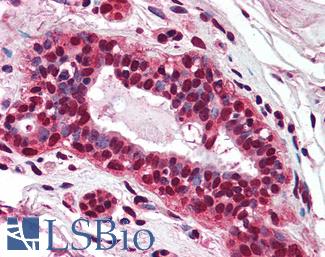

ERBB2 / HER2

Anti-ERBB2 / HER2 antibody IHC of human breast, carcinoma. Immunohistochemistry of formalin-fixed, paraffin-embedded tissue after heat-induced antigen retrieval. Antibody LS-B2133 concentration 5 ug/ml.